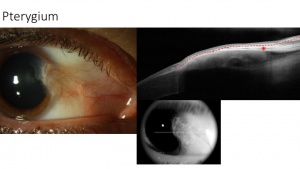

Pterygium – subepithelial

AS-OCT images of pterygia demonstrate a thin or normal layer of epithelium with varying levels of hyperreflectivity overlying a dense, hyperreflective, fibrillary subepithelial lesion that is between the corneal epithelium and Bowman’s layer. Studies have shown that high-resolution AS-OCT can reproducibly differentiate between pterygia and OSSN by identifying statistically significant differences in epithelial thickness and location of the primary lesion (epithelial location for OSSN and subepithelial location for pterygia).[10] [11](Figure 7).